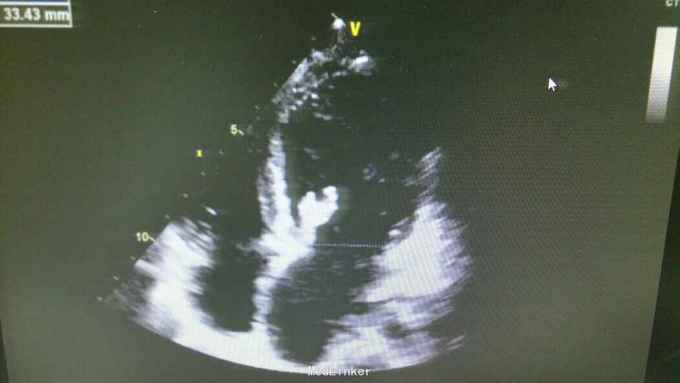

查体:T37.0℃,P110次/分,R26次/分,BP96/68mmHg。发育正常,营养一般,神志清楚,对答切题,轮椅送入院,查体合作。全身皮肤粘膜无黄染、皮疹,出血点及淤斑,未见Janeway结节,未见Osler结节及甲床下出血,无发绀,未见杵状指、趾,周围血管征阴性。浅表淋巴结未及肿大。巩膜无黄染,结膜无出血。口腔黏膜光滑,咽不红,扁桃体部大,颈静脉无明显搏动,未见怒张,气管居中,胸背部听诊双下肺闻及细小湿啰音。心前区无隆起或抬举性搏动,心尖搏动以左侧第六肋间锁骨中线外1.5cm处明显,未扪及震颤,心界向两侧稍扩大,心率110次/分,律齐,心音有力,P2稍亢进,无固定分裂,心尖区闻及3-4/6级收缩期吹风样杂音,向心底部传导,未闻及舒张期杂音,未闻及心包摩擦音。腹平软,无压痛及反跳痛,肝脾肋下未及,肠鸣音正常。脊柱、四肢关节无异常,活动好,双下肢无浮肿。 2015年10月30日汕头市中心医院心彩超:二尖瓣及瓣下腱索及左室心内膜多发赘生物形成,二尖瓣前瓣穿孔,重度二尖瓣关闭不全,左心系统扩大,心肌舒张功能下降,收缩功能正常,感染性细菌性心内膜炎,微量心包积液。 2015-11-1血常规:中性粒细胞比例 0.949,血红蛋白浓度 117.000(g/L),中性粒细胞计数 18.360(10E9/L),白细胞计数 19.350(10E9/L),血小板计数 343.000(10E9/L),红细胞计数 4.350(10E12/L)。 B超:双侧颈动脉血流通畅,双侧椎动脉未见狭窄。双侧甲状腺不大、未见占位,血供尚丰富。双侧颈部淋巴结声像,双侧乳腺未见明显占位,超声BI-RADS分类1类,双侧腋窝淋巴结声像。双肾未见结石与积水,双肾动脉主干血流连续,膀胱未见明显结石,双侧肾上腺区未见明显占位。肝脾胰不大,未见占位,胆囊未见明显结石,子宫及双侧附件区未见明显占位,宫后积液(少量)。 胸部CT:1、两下肺叶后基底段局部节段性肺炎。右肺中叶少许纤维化病灶。2、双侧胸腔少量积液。 胸片:考虑双肺炎症。 心电图:心率84次/分,窦性心律,肢体导联低电压,前间壁R波上升不良。 心彩超:1、考虑感染性心内膜炎:二尖瓣赘生物形成,伴中重度二尖瓣反流。中度三尖瓣反流。3、左房内径增大,肺动脉增宽。 头颅MR:左侧额叶、左侧放射冠侧脑室前角旁脑白质异常信号,考虑感染性病变及缺血灶可能性大。 2015-11-2查血常规:中性粒细胞比例 0.840,血红蛋白浓度 103.000(g/L),中性粒细胞计数 14.730(10E9/L),白细胞计数 17.540(10E9/L),红细胞计数 3.890(10E12/L),血小板计数 353.000(10E9/L)。 10月31日左上肢、右上肢、下肢血培养均提示:草绿色链球菌,对万古霉素敏感。 2015-11-6肾功能:肌酐 130.000(umol/L),尿素氮 5.250(mmol/L),二氧化碳结合力 30.500(mmol/L),电解质:钠 138.000(mmol/L),氯 96.000(mmol/L),钾 3.500(mmol/L),钙 2.310(mmol/L),肝功能:白、球蛋白比例 1.300,未结合胆红素 10.500(umol/L),总胆红素 17.900(umol/L),丙氨酸氨基转移酶 31.000(U/L),总蛋白 75.000(g/L),球蛋白 32.000(g/L),白蛋白 43.000(g/L),结合胆红素 7.400(umol/L),门冬氨酸氨基转移酶 31.000(U/L),脑钠肽:191.400(pg/ml)。 24小时心电图:窦性心律,房性早搏,部分成对,短阵房速,多源室早,部分成对,部分呈三联律,短阵室速。

根据患者病史、查体、辅助检查可明确术前诊断:1、亚急性感染性心内膜炎:二尖瓣赘生物形成,二尖瓣关闭不全(中-重度),三尖瓣关闭不全(中度),心功能Ⅱ-Ⅲ级。2、肾功能不全。3、贫血。予选择敏感抗生素抗感染治疗,先用万古霉素1g q12h+阿米卡星0.3 q12h,抗感染治疗,后查肌酐升高,肌酐 145.000(umol/L),肾功能受损,考虑与万古霉素有关,请临床药师会诊建议调整抗生素,11-8改头孢曲松1g q12h抗感染。另积极强心、利尿、控制心率、营养心肌、提高免疫力、输血等治疗,患者仍间有高热、畏寒,存在肾功能损害、贫血,手术时机不能拖延。2015-11-12全麻体外循环下行左心赘生物清除、二尖瓣置换、三尖瓣成形、卵圆孔未闭修补术。 手术记录: 平卧位,麻醉诱导插管,左桡动脉穿刺置管测血压,右颈内静脉穿刺置管测中心静脉压及输液,留置导尿管,安尔碘消毒皮肤,常规铺巾,贴皮肤保护膜。正中切口,纵锯胸骨进胸,正中切开心包,术中探查:少-中量淡黄色心包积液,右心房、右心室明显增大,主动脉:肺动脉=22:28(mm),肺动脉扪诊张力较高,主动脉根部无震颤。常规主动脉、上、下腔静脉套带,缝合荷包,上腔静脉荷包用4-0prolene线缝在上腔静脉根部。肝素化(3mg/kg),依次插主动脉管(20号)、上腔管(26号金属直角管)、下腔管(32号),转机并行循环,右上肺静脉插左心引流管,主动脉根部插灌注针。阻断上、下腔静脉,阻断主动脉,顺灌4:1含血停跳液300ml,心表冰泥降温保护心肌,心脏停跳,纵形切开右房见卵圆孔未闭,切开房间隔,探查见二尖瓣败坏严重,前瓣靠瓣沿有一较大赘生物,瓣下腱索上也有芝麻粒大小赘生物,后瓣靠前交界瓣叶上右大小不等赘生物,腱索挛缩,将瓣叶及赘生物粘在左室后壁,瓣口关闭不全,左房后壁靠瓣环前交界附近有散在的米粒或芝麻大小赘生物,无附壁血栓。切除病变瓣膜及腱索,仔细清除左心室、瓣环及左房后壁赘生物,高效碘消毒左心腔,大量冰生理盐水反复冲洗左心室,测量瓣环可容27号,全周带垫片褥式缝合14针,再次冲洗左心室,用carbomedics 27号瓣,上瓣打结,检查瓣膜固定满意,瓣叶开闭正常,将左心引流管通过瓣口置入左心室内,用4-0prolene线封上下角后连续往返缝合房间隔切口,修补未闭卵圆孔。探查三尖瓣环扩大达3横指多,用3-0proline线带垫片缝缩三尖瓣后瓣环(半个devage成形),做三尖瓣成形至能通过约2个横指,主动脉灌注针及左心管排气,开放主动脉阻断钳,心脏自动复跳,为结性心率,心率慢,约50-60次/分。用4-0prolene线关闭右心房切口。辅助循环后转为窦性心律。复温及并行循环辅助后血流动力学稳定停机,依次拔出左心管、下、上腔管,主动脉根部注射鱼精蛋白,拔出主动脉管,检查心脏各切口并止血,心脏各切口覆盖艾薇停(1包)、胶原蛋白海绵(2包),3-0滑线连续缝合心包,电烙骨腊止血,留置心包及纵膈引流管,5根钢丝对合胸骨,逐层缝合关胸,术毕。 术后继续孢曲松1.5g q12h+庆大霉素4万U q8h抗感染,另积极强心、利尿、控制心率、营养心肌、抗凝、提高免疫力、补充营养等治疗,患者无发热、寒战,全身状况好转,但出现反复双侧胸腔积液及心包积液,予心包穿刺引流及胸腔闭式引流。目前患者在平稳恢复中,治愈出院。